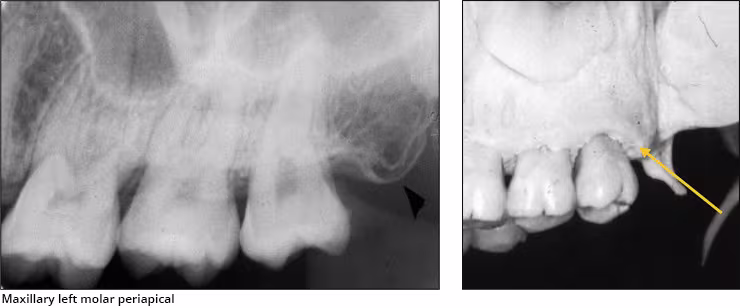

Maxillary tuberosity – The maxillary tuberosity is the rounded end of the alveolar process of the maxilla. This radiopaque structure appears bilaterally on maxillary molar periapical images and often on maxillary premolar periapical images and molar bitewings. The tuberosity curves upward at the end of the maxillary alveolar process. The tuberosity gives a smile appearance to the maxilla and the dentition particularly on bitewings.

Pterygoid plates – The lateral and medial pterygoid plates are located behind the maxillary tuberosity. They project a single image configured like a thin wing of bone extending posteriorly from the tuberosity. This bilateral radiopacity is occasionally recorded on maxillary molar periapical images when the receptor is positioned adequately posterior.

Hamular process – The hamular process or pterygoid hamulus is a tiny finger or hook-like projection of bone that extends inferiorly from the medial pterygoid plate. This bilateral radiopacity occasionally appears on maxillary molar periapical images and molar bitewings when the receptor is positioned sufficiently posterior to record it.